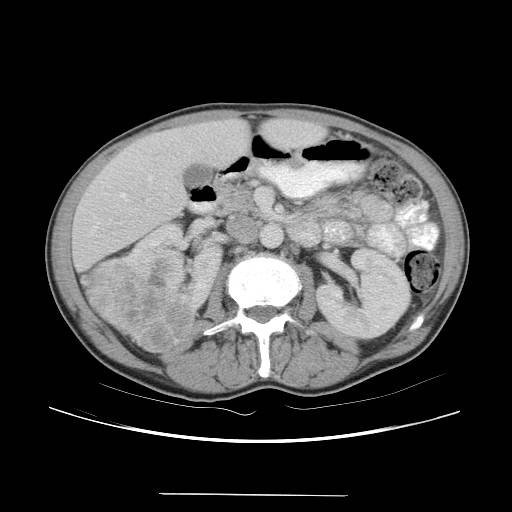

Case 2 CT

IMPRESSION:

1. Likely renal cell carcinoma with multiple metastases to lung, right

3rd rib, and likely right iliac. There is no definite invasion of

adjacent organs or the vasculature.